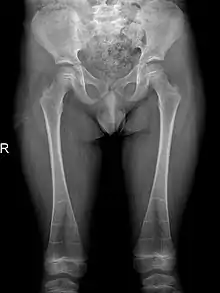

It is also reported that individuals may also suffer from pelvic abnormalities. This includes the development of narrow iliac wings, as well as widened femoral necks. However, incidence of both symptoms are rare in patients with DSS, occurring in less than 30% of cases.[6][7]

The occurrence of DSS also leads to deformities of the limbs. 80% of patients reported with abnormalities of the metaphysis such as metaphyseal flaring, radiolucent metaphyses, abnormal metaphyseal trabeculation, which is abnormal trabecula patterns in the metaphyseal region, and epimetaphyseal sclerosis. Other limbic abnormalities include progressive bowing of long bones, which is present in rare cases.[6][7]

Sclerosis of epiphyses, diaphyses, and metaphyses with increased radiolucency are key characteristics of the disease.[18] In addition, mottled metaphyseal sclerosis and widening are also present in patients.[4][9] Development of irregular patchy sclerosis along the bone can also be identified,[9] as well as metaphyseal flaring evolve towards Erlenmeyer flask deformity with nonuniform patches of sclerosis, which are especially prevalent in older patients.[10]

The metadiaphyses, a portmanteau of the metaphysis and diaphysis,[20] are bulbous and expanded with bowing and relative radiolucency. The expanded regions are also sclerotic and gives the characteristic bone-in-bone appearance.[4]